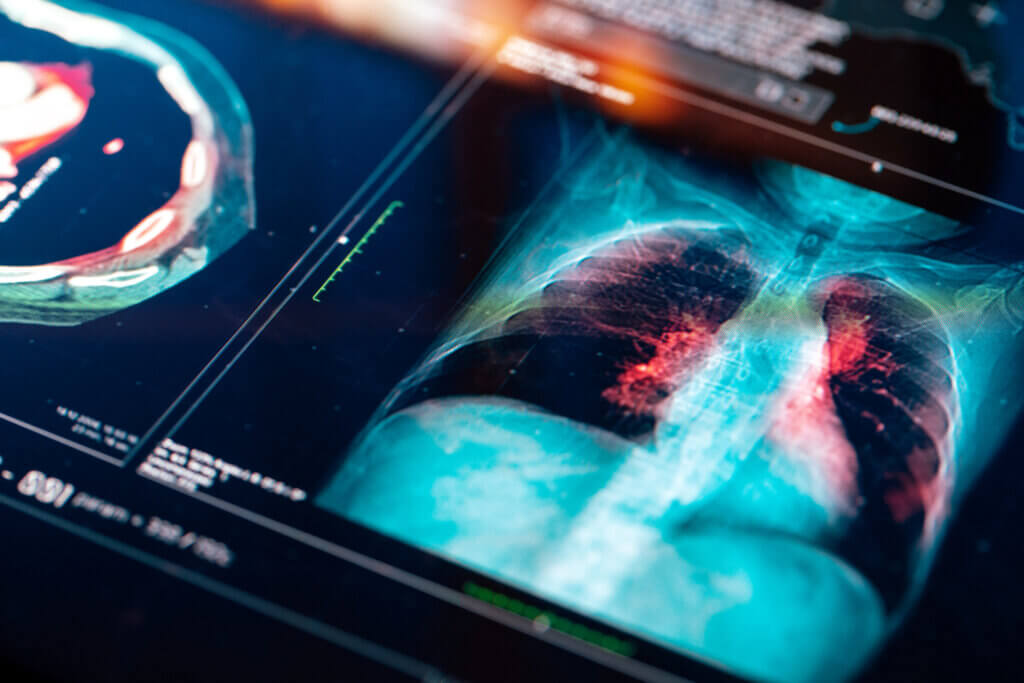

Kunstmatige intelligentie (AI) biedt vele kansen voor de gezondheidszorg. Denk aan AI-systemen die kanker detecteren, aangeven of iemand geopereerd moet worden voor een botbreuk of kunnen voorspellen of iemand een hartritmestoornis krijgt. Maar juist in deze sector spelen ook zekere risico’s en ethische vraagstukken, die de vraag doen rijzen: hoe kunnen we AI verantwoord inzetten?

Zo’n vaart zal het niet lopen, menen experts. Toch kunnen we niet ontkennen dat er binnen kunstmatige intelligentie, of AI, grote stappen worden gemaakt. Uit onderzoeken blijkt al dat AI-modellen vaak beter zijn in het opsporen van bijvoorbeeld kanker of voorspellen of een botbreuk instabiel wordt. Daarnaast kunnen generatieve AI-modellen als ChatGPT artsen ondersteunen bij het maken van samenvattingen of het opstellen van een ontslagbrief voor een patiënt. Dergelijke ontwikkelingen kunnen de zorg mogelijk verbeteren en veel administratief werk wegnemen bij artsen.

“Een klassiek voorbeeld is van een app die ontwikkeld werd om melanomen – dus huidkanker – te diagnosticeren aan de hand van foto’s. Die app was ontwikkeld op basis van data van mensen met een witte huidskleur. Mensen met een donkere huid zijn dan echt slechter af. Daar presteert die diagnostische test gewoon minder goed”, geeft Boenink als voorbeeld.

In de gezondheidszorg zijn bovendien heel veel variabelen waar bias in kan sluipen. Zelfs de locatie waar een algoritme ontwikkeld is, heeft invloed, zeggen Boenink en Oosterhoff. De levensverwachting in Nederland is bijvoorbeeld anders dan die in Australië of Amerika, net als ons dieet, scholing en zorgsysteem. “Als een model in Amerika is ontwikkeld en we gaan het nu hier toepassen, dan zou ik me daar heel veel zorgen over maken. Er zitten enorme verschillen tussen die populaties, waardoor ik me afvraag of die wel voldoende met elkaar overeenkomen om een algoritme hier toepasbaar te maken”, zegt Boenink.

Oosterhoff sluit zich daarbij aan: “Je moet heel goed testen of een AI-model uit Amerika ook werkt in bijvoorbeeld Australië. Je kunt in sommige gevallen beter een nieuw algoritme maken voor specifiek die populatie.” Volgens haar heeft dat ook te maken met het feit dat het gezondheidssysteem in Nederland heel anders is dan in andere landen. “Als je in Nederland een gebroken pols hebt, worden twintig van de honderd patiënten geopereerd. Maar in Australië zijn dat er tachtig van de honderd.” Een Australisch AI-model zal er dus op getraind zijn om eerder te adviseren om te opereren.